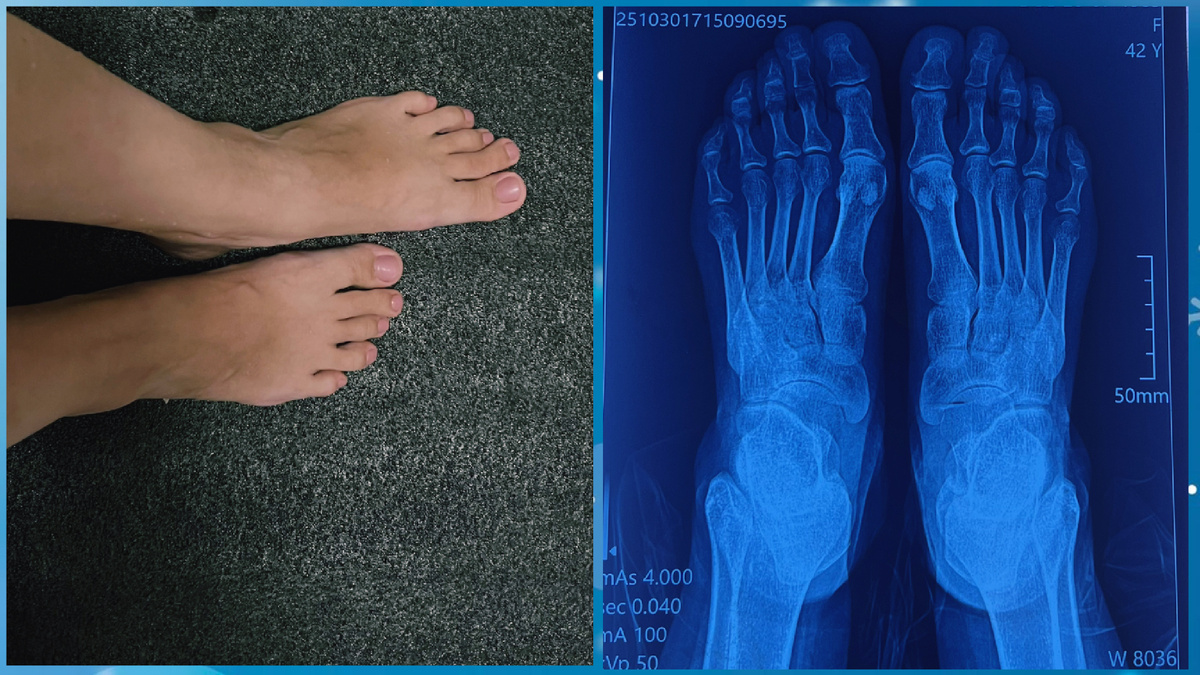

Вот мои стопы и рентген, на фото видно второй  палец деформирован, деформирующих артроз, на рентгене не так как на фото, деформация меньше кажется

Ок, хорошо, красиво - да, у меня тонкая кость и ножки смотрятся красиво и аккуратно, на рентгене и на фото видно, но вот с этим пальцем незадача